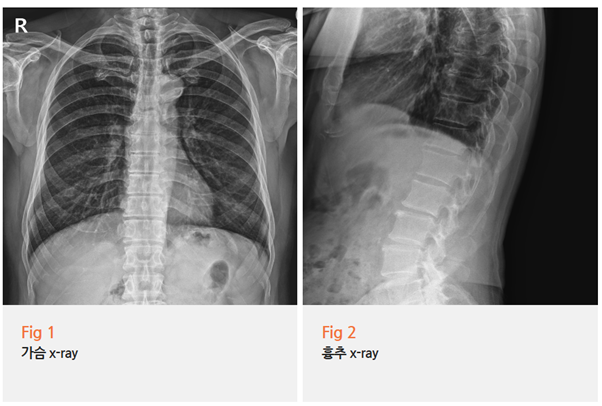

제가 먼저 X-RAY부터 찍어봤습니다.

골절이나 명확한 구조적 문제가 있는지 확인하기 위해서죠.

결과는? 역시나 특별한 이상 없음.

그림5.png